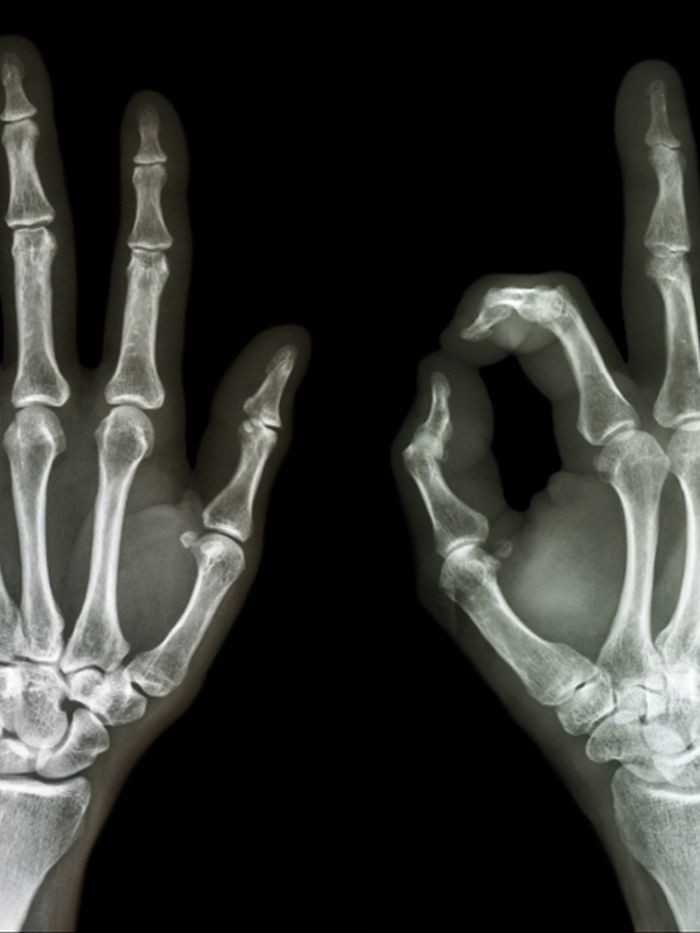

Способность противопоставлять палец формируется уже 4 миллиона лет, и неизвестно, достиг ли признак своего логического максимума. Еще 100 тысяч лет назад у неандертальцев большой палец отводился очень ограниченно. Его противопоставленность другим пальцам фактически делает нас людьми, позволяя качественно захватывать предметы. Пальцы кисти все разной длины, она зависит от уровня тестостерона в организме будущей матери. Указательный палец отличается большей по сравнению с другими чувствительностью — недаром когда мы видим что-то удивительное, невольно показываем на это пальцем, как бы тянемся дотронуться и прочувствовать. Средний палец отвечает за силу удержания, безымянный оценивает силу захвата и направление силы тяжести предмета. Мизинец помогает балансированию, когда рука работает в плоскости.

Сила кисти удивляет — тренированные люди могут удерживать вес тела, вися на кончиках пальцев. При этом в самих пальцах есть только сухожилия, все мышцы находятся в ладони и предплечье. Каждую руку обслуживает 34 мышцы, благодаря им движение рук — это сложный, скоординированный танец.